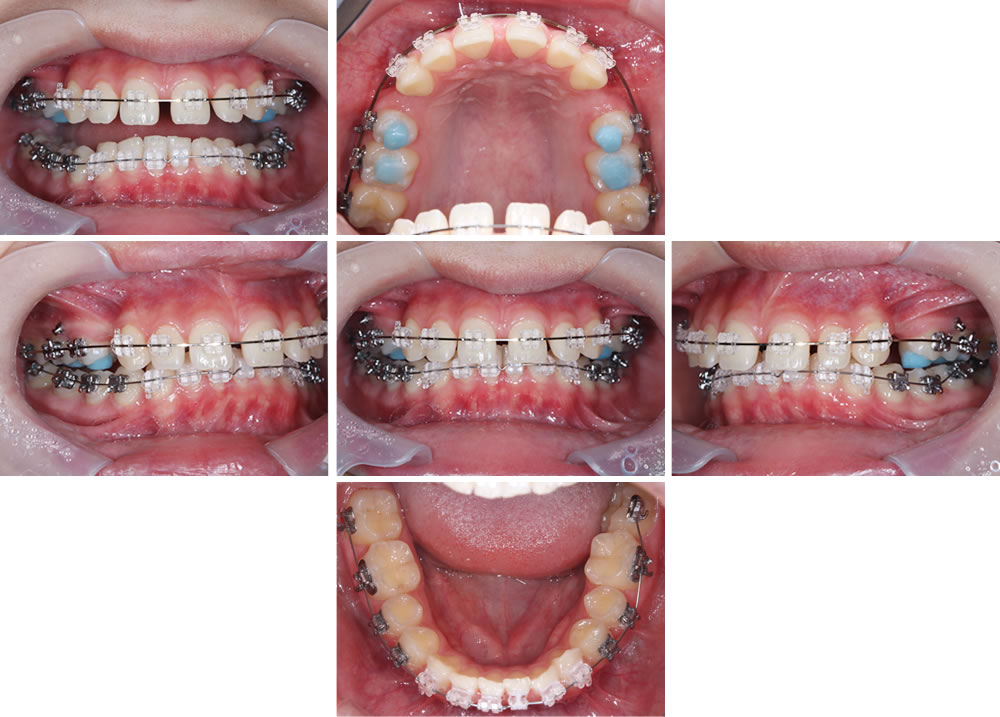

矯正治療の開始

まずは上顎に装置をつけて歯を並べていきます。

続いて、上の歯は小臼歯を2本抜歯して引っ込める方向に力をかけながら、下顎の並びもさらに整えていきます。